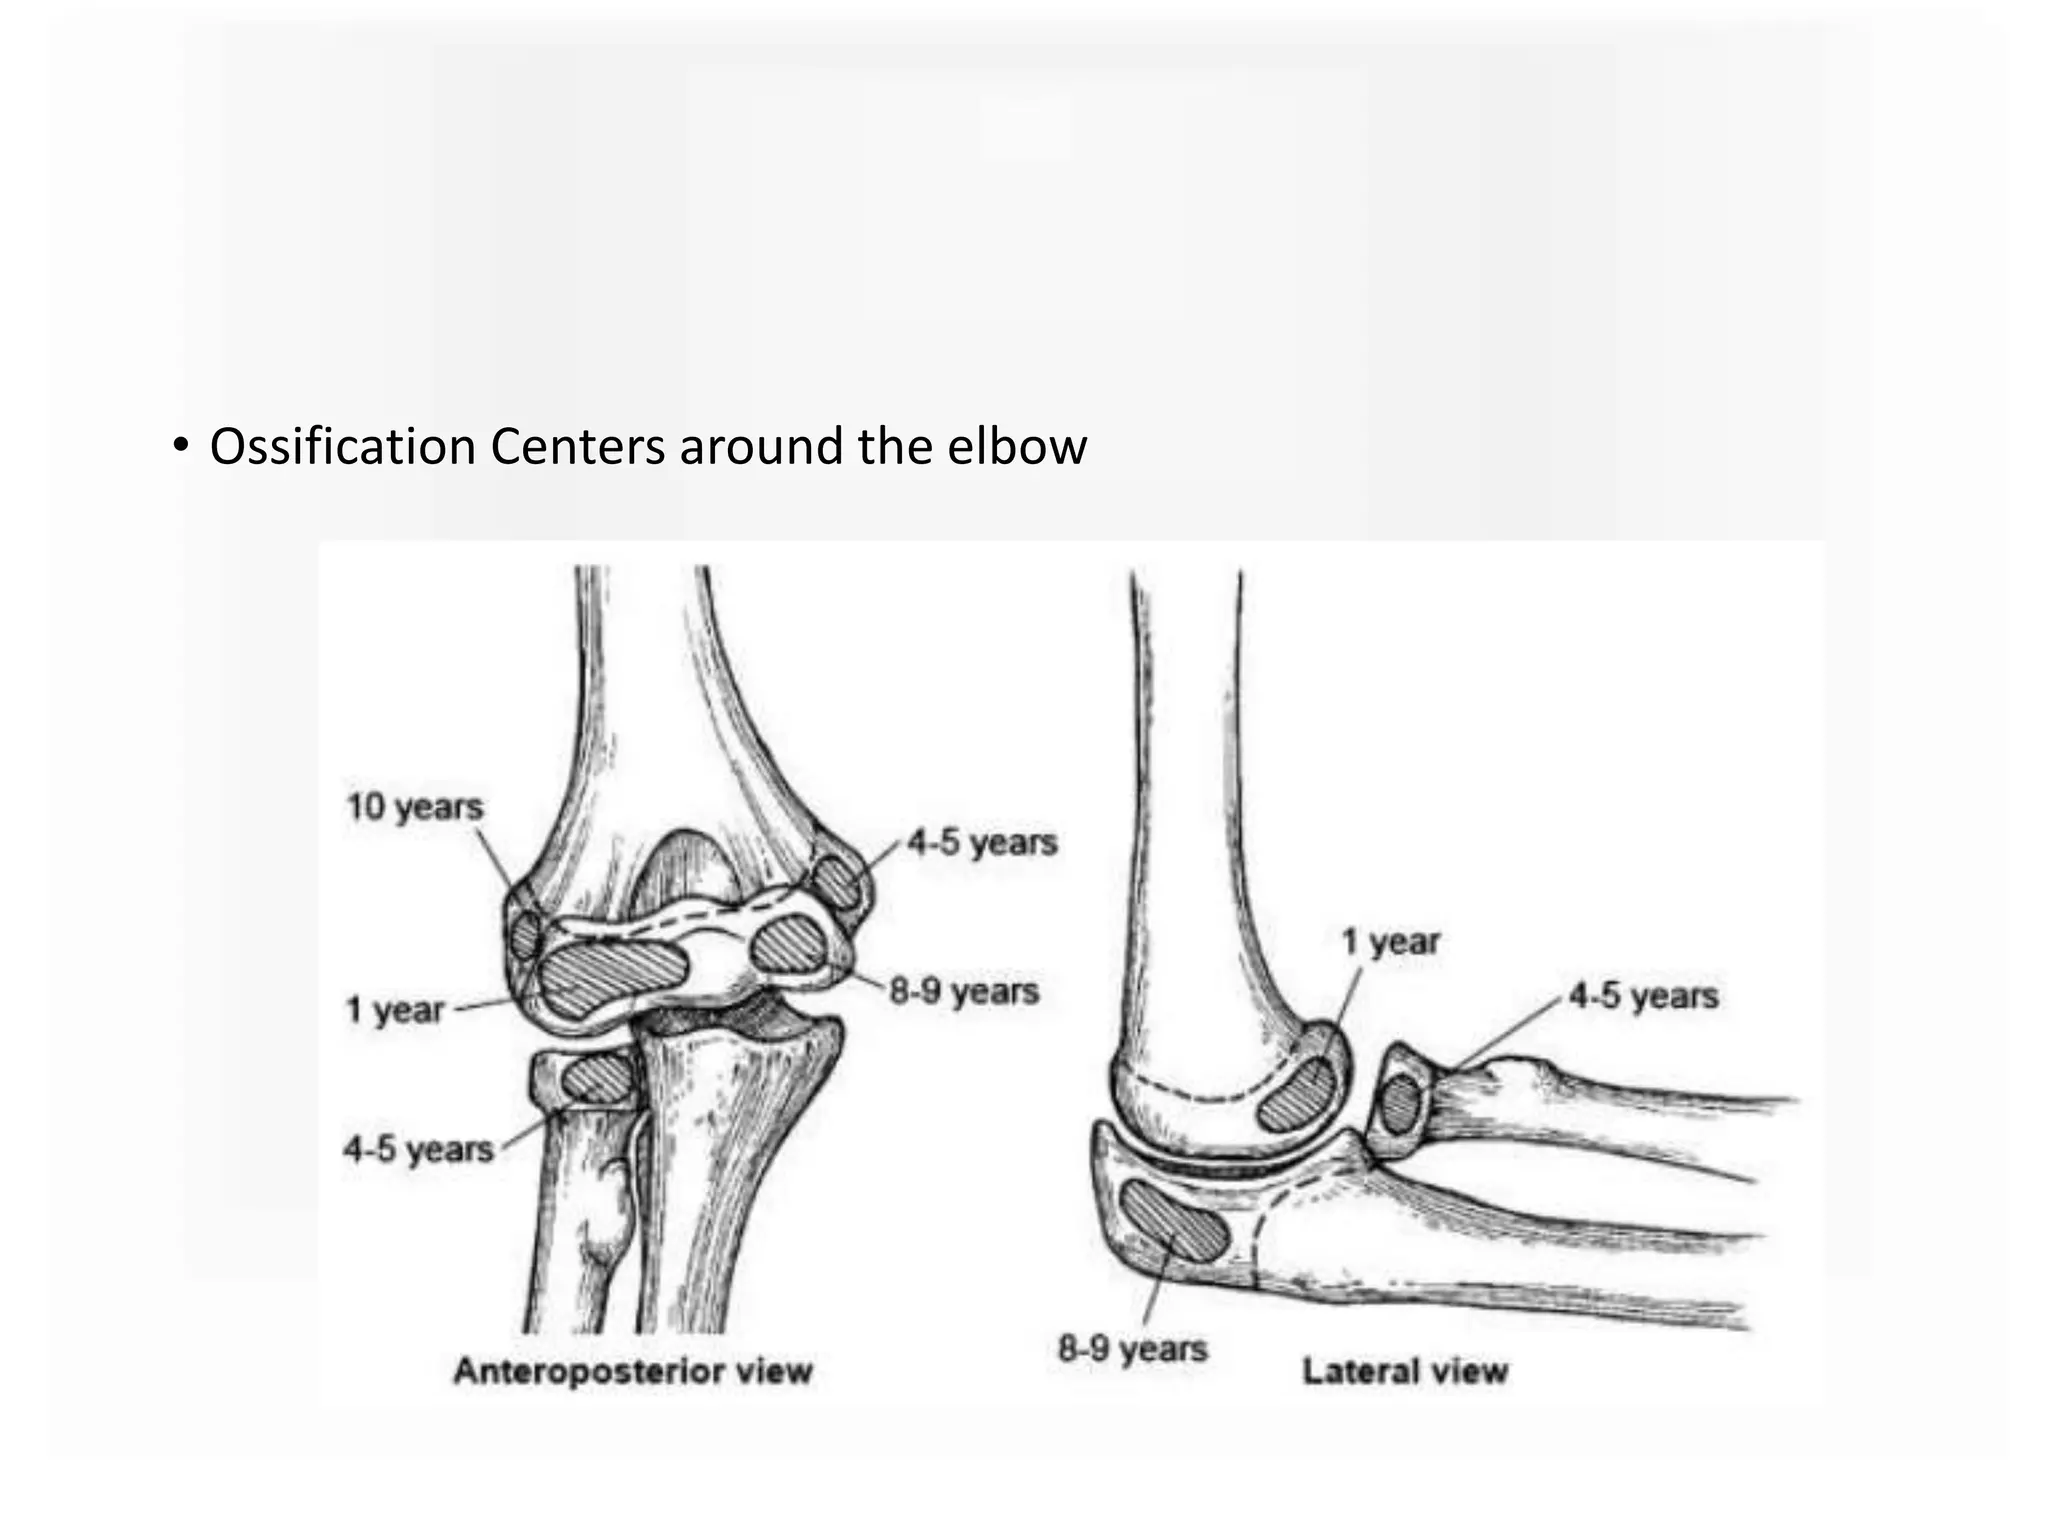

• Ossification Centers around the elbow

• Ossification Centersaround the elbow